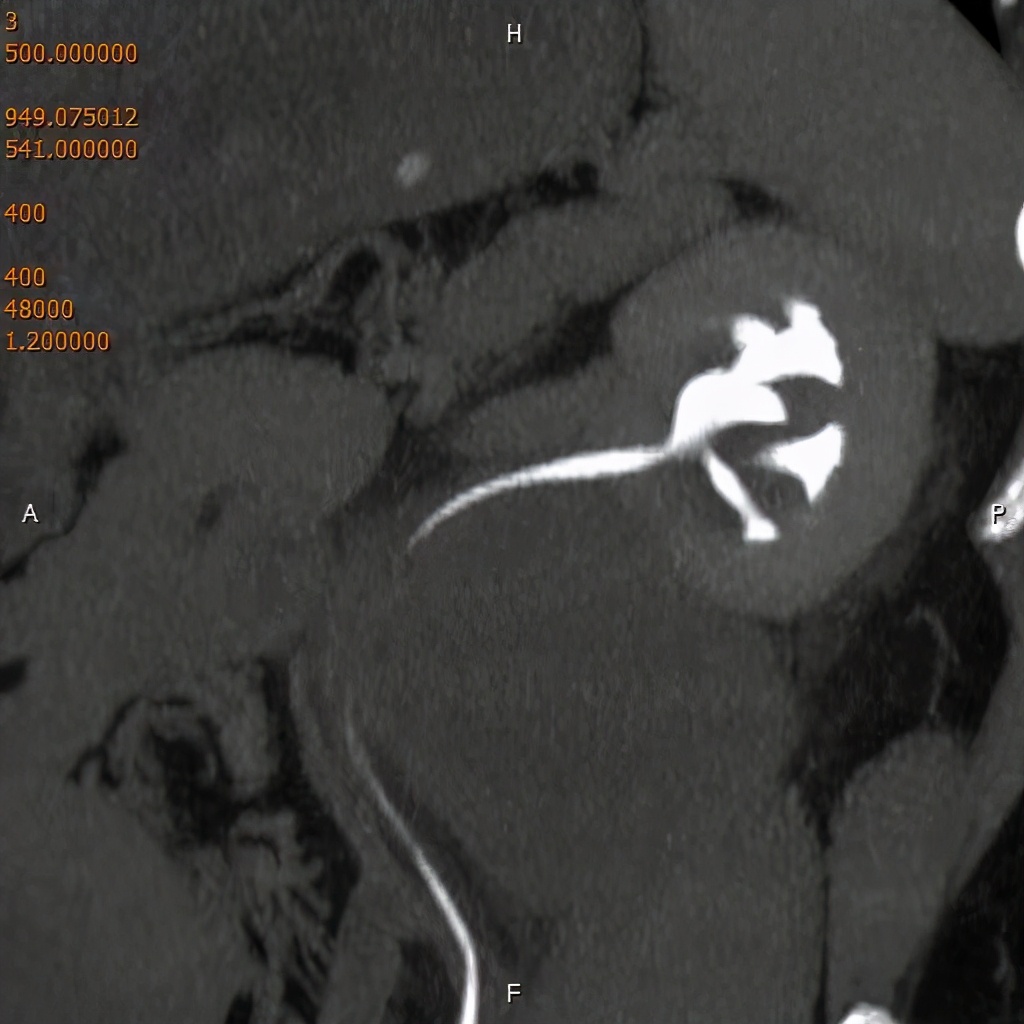

上图为泌尿系平扫后重建,可见左侧输尿管中段结石。

下图为静脉注射造影剂后,进行一定时间延迟后进行扫描、重建,见结石影与造影剂对比良好。